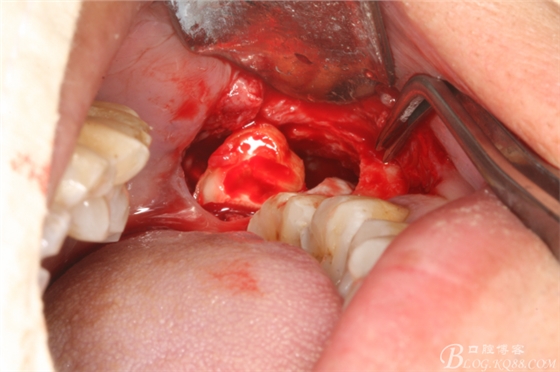

圖1. 口內(nèi)38完全埋伏

圖2.切開、翻瓣、去骨

圖三、完全暴露38牙根和牙冠

圖4.橫斷牙根和牙冠

圖5.首先取出牙根

圖7.然后取出牙冠